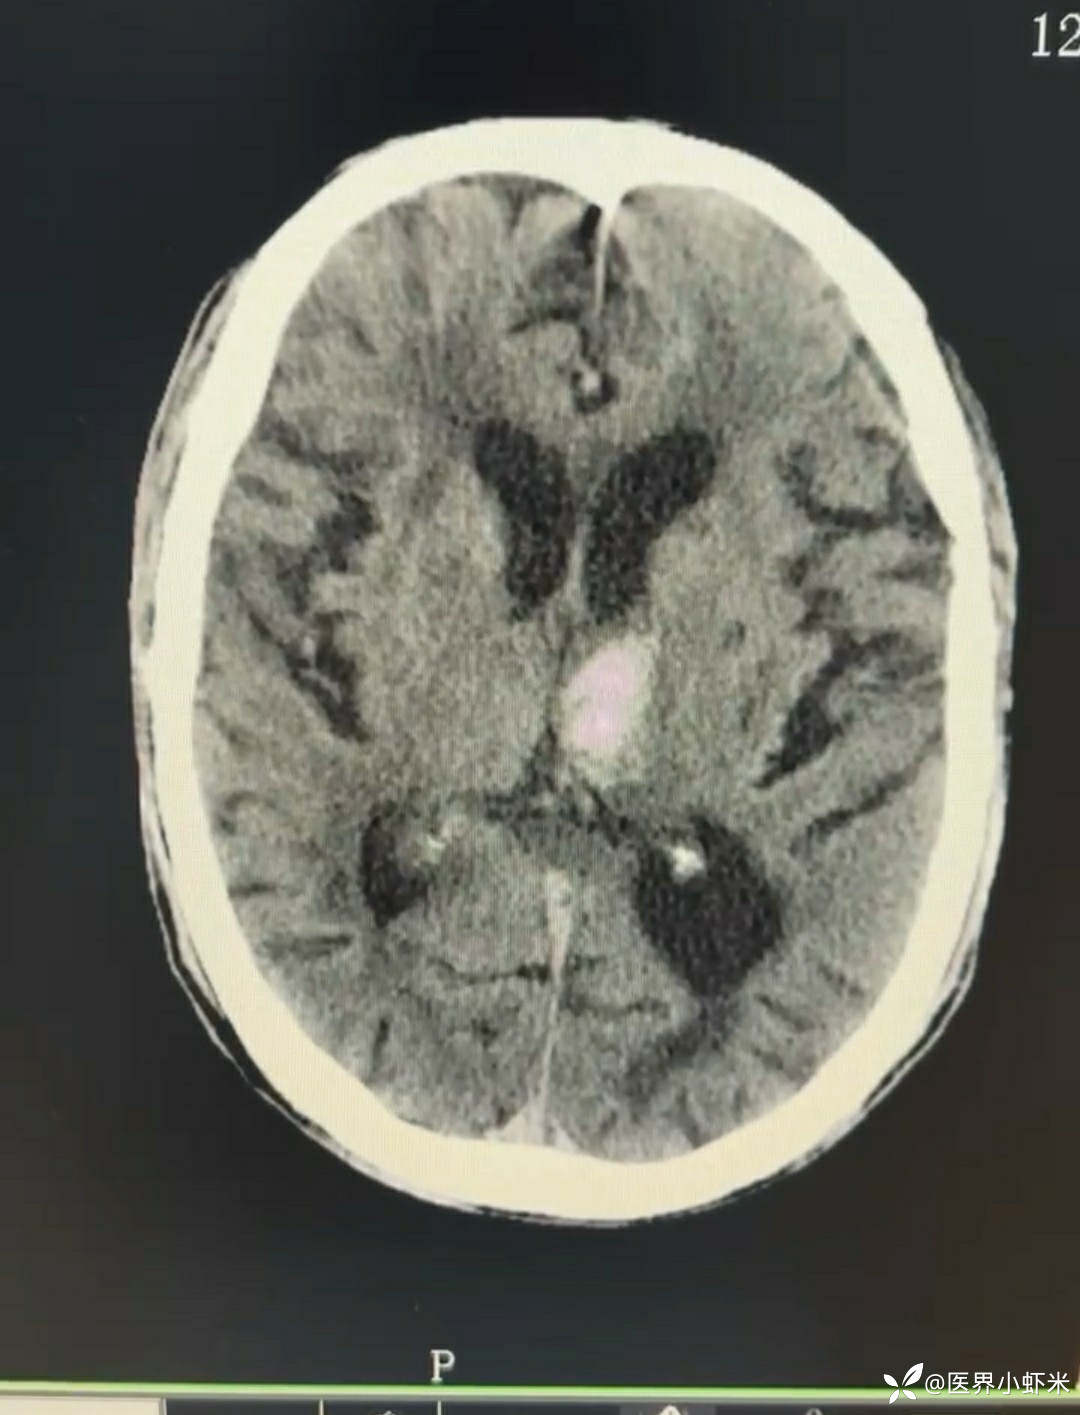

目前考虑:1.中央型肺癌伴2.肝继发恶性肿瘤?2.左丘脑继发恶性肿瘤?3.左丘脑出血?4.肾功能不全5.肝功能异常6右肾萎缩7.肺部感染8.慢性阻塞性肺病7.高血压3级(极高危)。